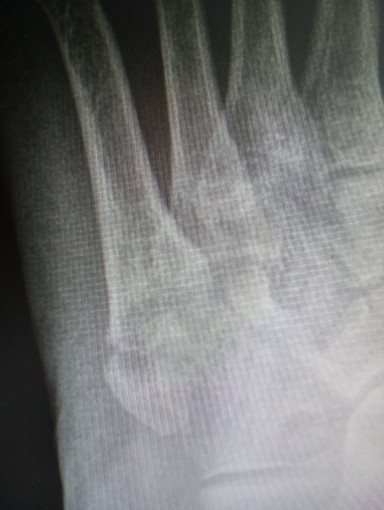

17 мая перелом 5 плюсневой кости. Проконсультируйте что делать дальше

Здравствуйте. Если с момента перелома прошло более 7 недель, важно сделать контрольный рентген. Если есть признаки сращения тогда можно постепенно нагружать стопу, начинать ЛФК и ношение удобной обуви. Если сращение неполное тогда требуется продление иммобилизации и контроль у травматолога.

что можно сказать по данному снимку?